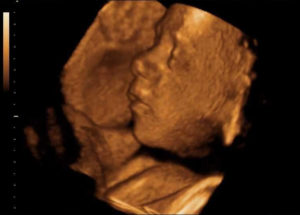

Если снимки выполняют посредством 3D УЗИ, то на фотографии можно рассмотреть радужную оболочку глаза.

Что интересно — на сроке 31 неделя беременности при УЗИ на фото и видео уже можно достаточно подробно рассмотреть черты лица ребенка.

Конечно, цвет глаз еще не рассмотреть (хотя радужная оболочка в этот период уже начинает приобретать свойства взрослого глаза и реагирует на яркий свет), но сейчас все более популярной становится технология 3D и 4D УЗИ, которая дает наибольшие возможности в визуализации плода.